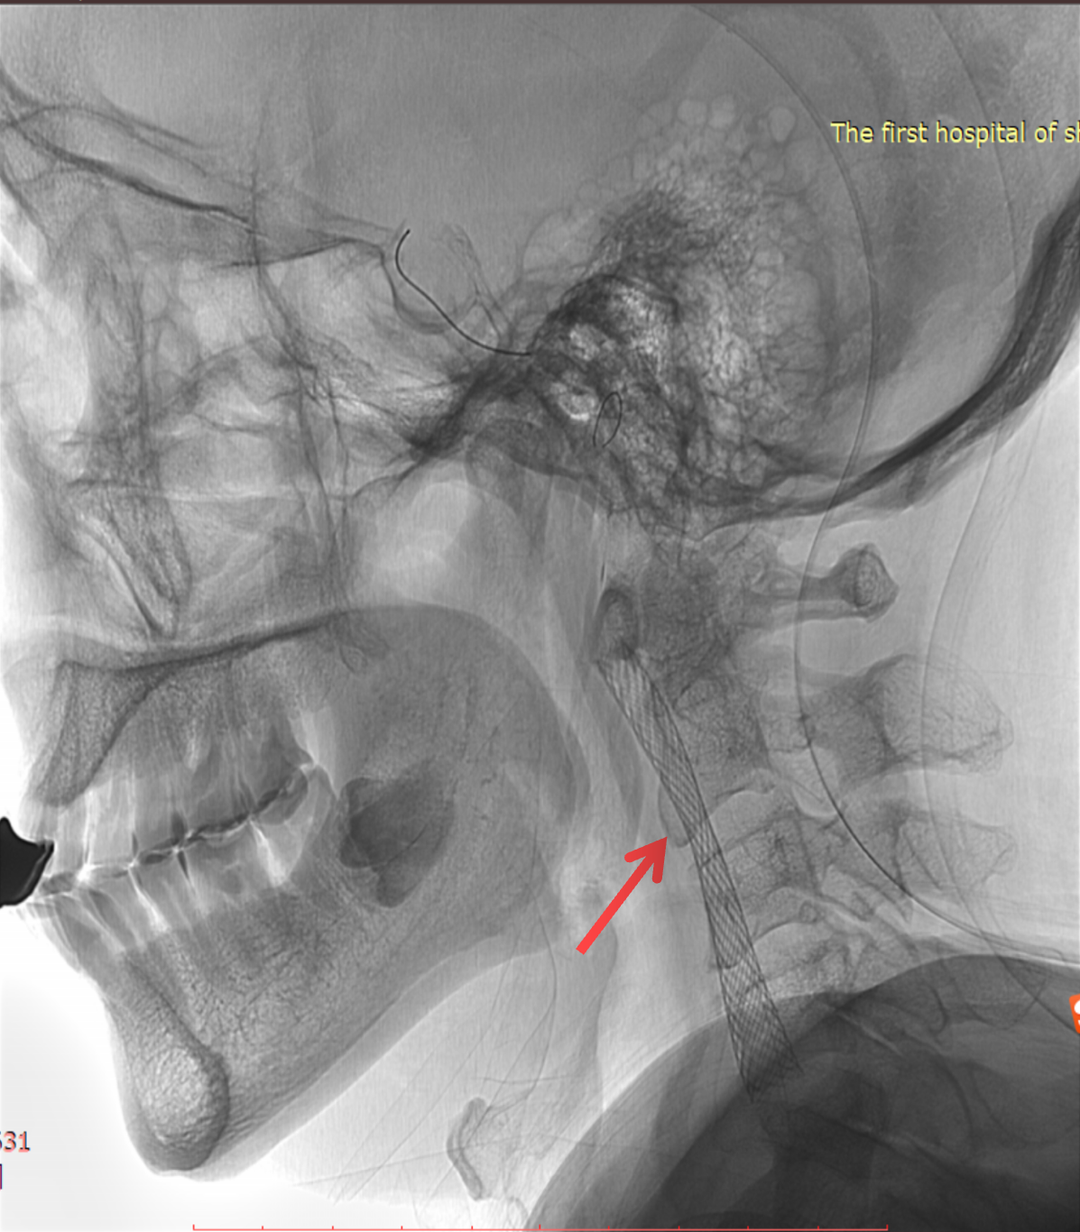

术后情况

术前、术后对比

波科支架怎么样径技-弓上病例大赏|第210期·右侧颈内动脉球囊扩张术+支架植入术_https://www.jmylbn.com_新闻资讯_第24张

波科支架怎么样径技-弓上病例大赏|第210期·右侧颈内动脉球囊扩张术+支架植入术_https://www.jmylbn.com_新闻资讯_第25张

波科支架怎么样径技-弓上病例大赏|第210期·右侧颈内动脉球囊扩张术+支架植入术_https://www.jmylbn.com_新闻资讯_第26张

波科支架怎么样径技-弓上病例大赏|第210期·右侧颈内动脉球囊扩张术+支架植入术_https://www.jmylbn.com_新闻资讯_第27张

总结

• 本患者血管相对迂曲,斑块不稳定,选用Filterwire保护伞+Wallstent支架,既保证了通过性,也能减少栓塞事件的发生;

• 选用Wallstent支架,同时可以让系统通过变得容易,便于球囊、长鞘或导引导管的通过,便于后扩张及避免收伞困难;

• 球囊后扩可改善支架贴壁情况,同时可以缩短手术操作时间,但也要注意可能带来的支架短缩的问题。